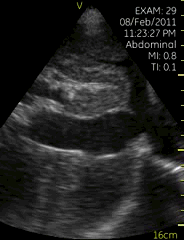

剑突下下腔静脉切面

| 图像名称: | 剑突下下腔静脉切面(二维) |

| 剑突下下腔静脉切面(二维) | | 介绍重点: | 下腔静脉宽度正常 |

| 下腔静脉增宽 | | 临床用途: | 容量负荷正常 |

| 右心压力增高 |